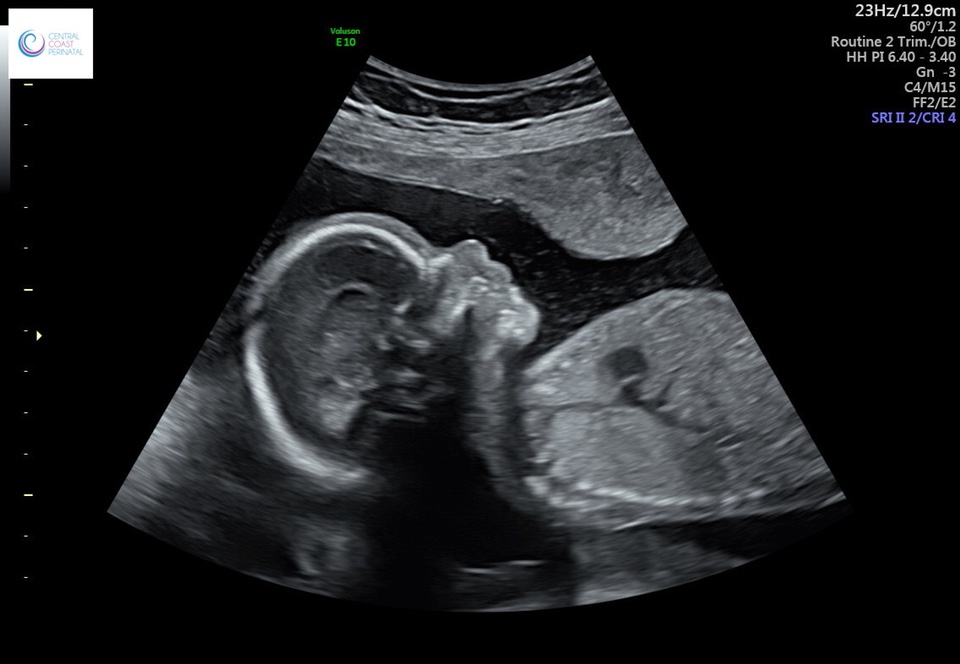

Any guesses would be appreciated. We didn’t find out gender but now I’m curious.Attachment 41163

Skull is really not reliable at all, but because I see a little chinny chin chin there I'll give a just for fun guess of boy. (on my kids' ultrasounds, my son's chins were more noticeable than my daughter's.)

Please note -this could very easily be wrong and probably is. Skull guesses are not accurate.

Gorgeous baby!